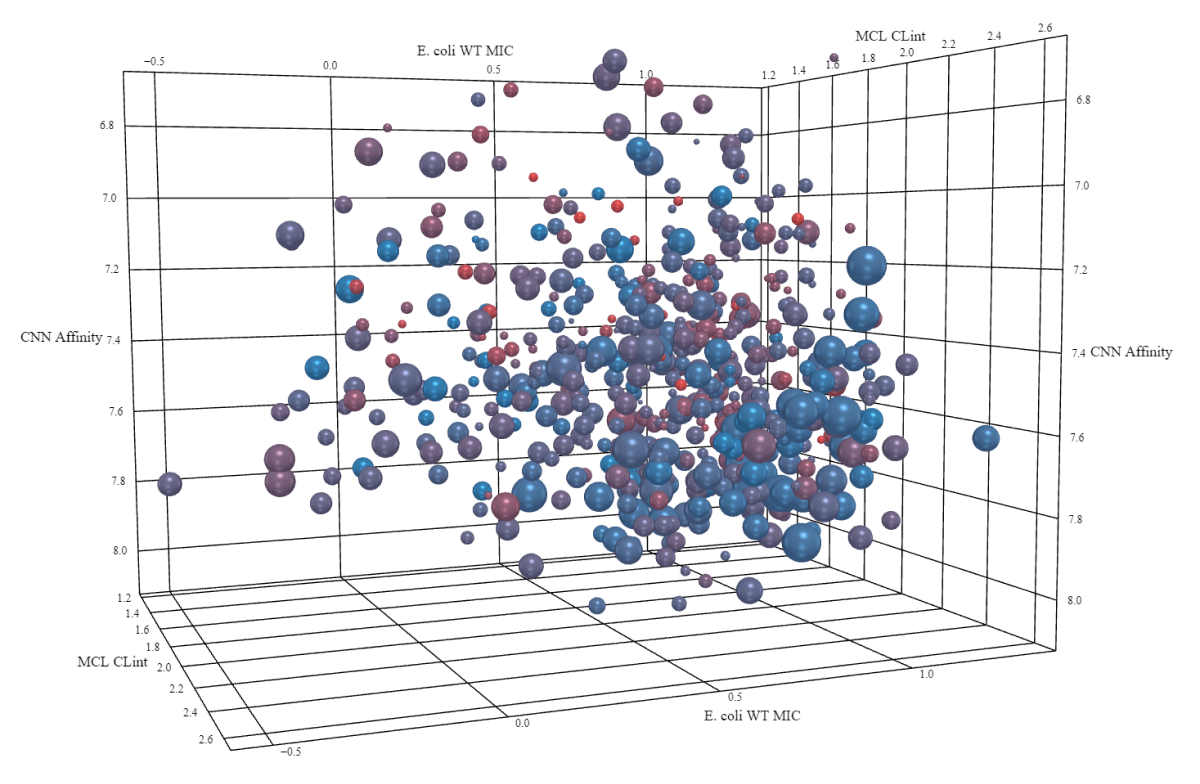

With over 1033 potential drug-like molecules and the need to balance multiple optimization parameters, successful drug discovery requires advanced data integration and innovative approaches that exceed human capabilities alone.

Drug discovery is a multiplex

optimization process

Concomitant optimization of six or more

properties is required for success

Even within a single molecular class

(e.g. a lead program), there are 100s of

millions of molecules